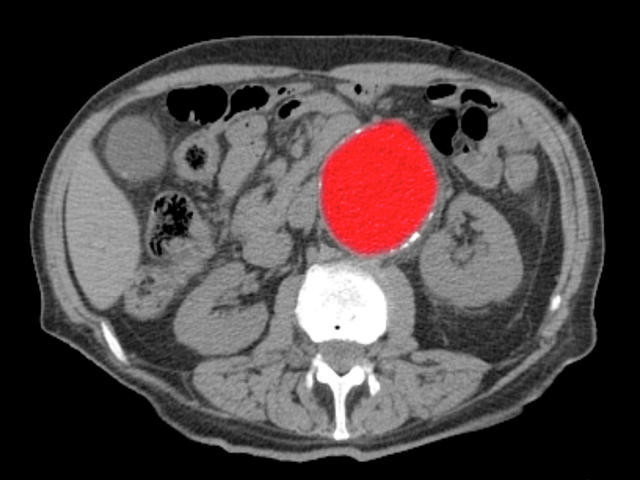

"Bu yırtıkların temelinde genellikle aortada genişleme yani anevrizma ile birlikte kontrolsüz yüksek tansiyon yer alır.Sırrı Süreyya Önder örneğinde olduğu gibi, daha önce 4.7 cm gibi sınırda ölçülen bir aort çapınız varsa ve kontrolsüz yüksek tansiyonunuz mevcutsa, risk çok yüksektir” dedi.

Aort çapı normalin üzerinde olan, kontrolsüz tansiyonu bulunan bireylerin düzenli takip altında olması gerektiğini söyleyen Prof. Dr. Köksal, “Bu hastaların yılda en az bir kez tomografi ile takip edilmesi gerekir.

Tansiyonun mutlaka düzenli kontrol altında tutulması şart. Çünkü aort damarındaki yırtılma, tıpkı koroner damarlarındaki gibi önceden sinyal vermez. Göğüste ani bir yırtılma hissi, saplanan ağrı, bayılma ve tansiyon düşüklüğü gibi belirtilerle kendini gösterir” şeklinde konuştu.